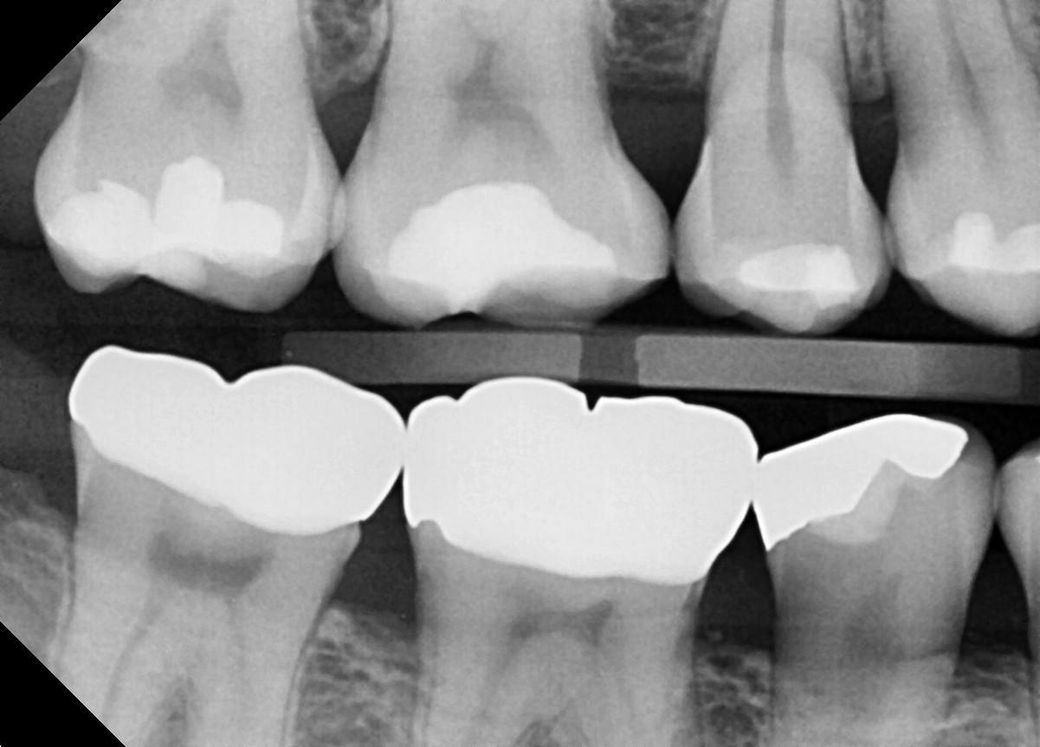

몇년전부터 오른쪽 아래에 반복적인 어금니 통증이 있었습니다. 그런데 어느 치아인지 정확하게 느낌이 오지 않았고 치과에서도 치아 자체에는 큰 문제는 없다 하셨습니다. 그런데 스케일링만 하면 통증이 사라졌었는데요, 최근에는 스케일링하고도 통증이 다시 돌아오는 주기가 점점 빨라지기 시작했습니다. 몇년전에는 스케일링을 한번 하면 3~6개월까지는 괜찮았는데, 지금은 스케일링 하고 나서 1~2개월 이후에 다시 아프기 시작합니다. 가까운 치과에서 씨티 촬영하니 오른쪽 아래 어금니에 뼈가 많이 녹아있다는걸 발견해 주셨는데요, 그게 원인인것 같다고 하시더라구요. 그부분에 하루에 한번씩 치간칫솔을(헥사메딘 묻혀서) 넣었다 뺏다해서 닦아주면서 관리해주라고 하십니다. 이게 적절한 방법인가요?

참고하실수 있도록 최근에 촬영한 문제가 되는 부위의 CT와 X레이사진 첨부합니다.

• 1번 째 사진

• 2번 째 사진

• 3번 째 사진